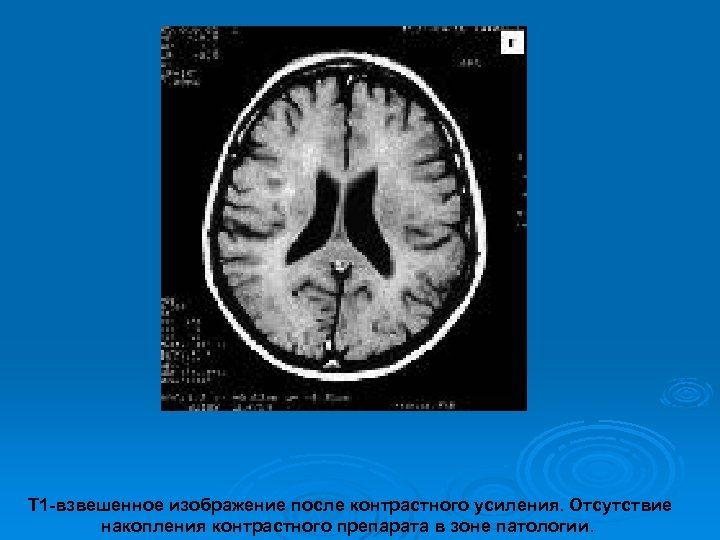

Изменения МРТ на фоне гормональной терапии

Т 1 -взвешенное изображение после контрастного усиления. Отсутствие накопления контрастного препарата в зоне патологии.